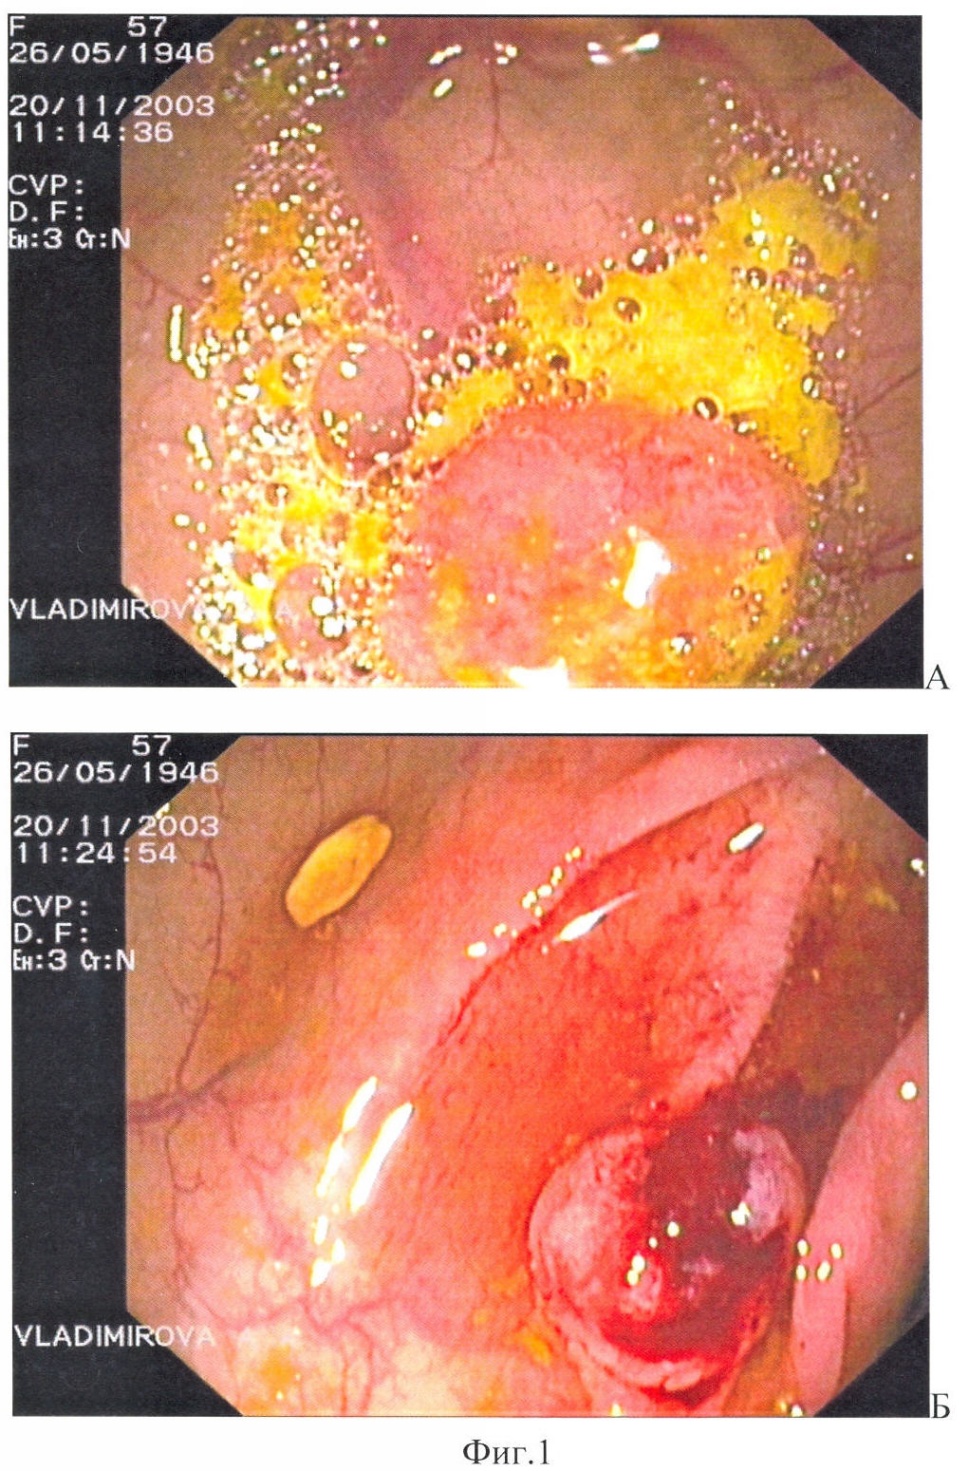

Способ поясняется следующими чертежами, где на фиг.1 показан полип области печеночного изгиба, суммарный балльный критерий более 179: а – при максимальном приближении дистальной головки и линзы колоноскопа, б – после биопсии; на фиг.2 – полип сигмовидной кишки, суммарный балльный критерий до 178 баллов (клинический пример 1); на фиг.3 – полип сигмовидной кишки, суммарный балльный критерий более 179 баллов, на фиг.4 – гистологический срез полипа сигмовидной кишки, окраска гематоксилин-эозином (клинический пример 2); на фиг.5 – полип сигмовидной кишки, суммарный балльный критерий до 178 баллов, на фиг.6 – полип сигмовидной кишки через 10 месяцев после первого обследования, суммарный балльный критерий более 179 баллов (клинический пример 3), а также табл.1, где перечислены эндоскопические признаки, их градации и числовые значения, используемые для вычисления суммарного балльного критерия, и табл.2, где показана морфологическая характеристика полипа и лечебная тактика в зависимости от суммарного балльного критерия исследования.

В области печеночного изгиба расположен полип на широком основании, размером до 0,6 см, розовый, округлый, рыхлый, контактно кровоточивый (фиг.1а, б).

В соответствии с предложенным способом определения вычислен суммарный балльный критерий по эндоскопическим признакам.

Критерий = группа по размеру + эндоскопический тип + цвет полипа + форма полипа + поверхность полипа + ранимость = 81+44+17+12+92+95=341 балл.

Суммарный балльный критерий более 179 баллов означает наличие облигатного предрака или развитие рака. Пациентке предложено выполнение полипэктомии.

Осложнений во время и после выполнения исследований не возникло. Полип удален методом петлевой электроэксцизии, извлечен из толстой кишки и направлен на гистологическое исследование.

При гистологическом исследовании в удаленном полипе обнаружена высокодифференцированная аденокарцинома без признаков инвазии опухолевых клеток в ножку полипа. Пациентка консультирована онкологом, выполнено комплексное обследование для исключения метахронных опухолей.